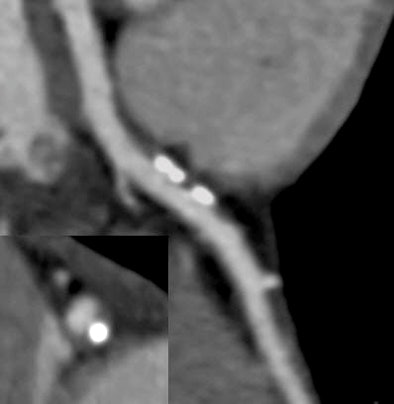

| Coronary CT angiography in cocaine user shows mixed plaque in the proximal left anterior descending artery. All images courtesy of Dr. Hans Ebersberger. |